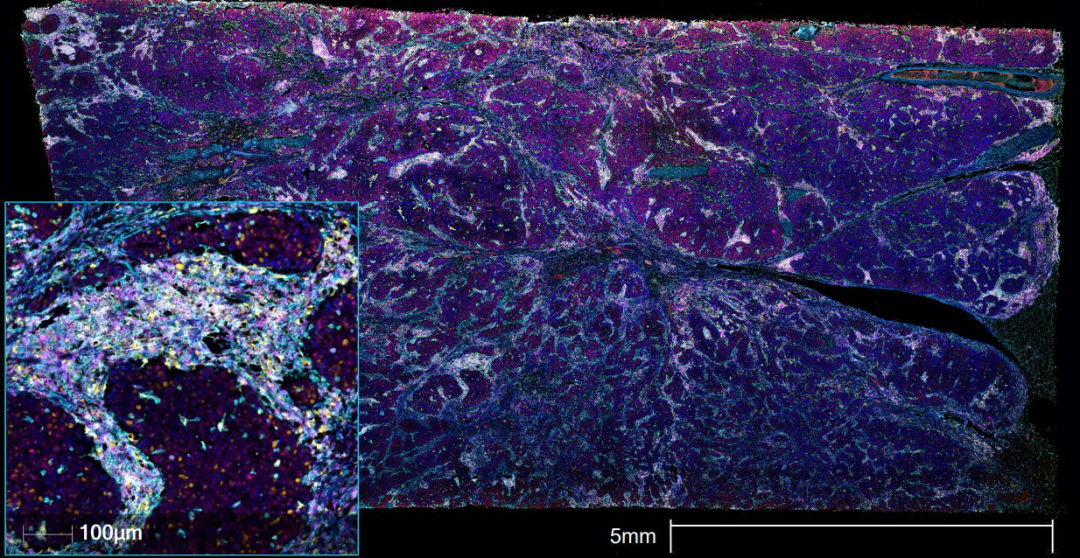

使用8重AluoraTM空间放大试剂盒对人侵袭性导管癌乳腺组织进行处理和染色,利用EVOS S1000空间成像系统,在20x物镜下进行图像采集,生成的整个组织切片的高分辨率图像。

图3 EVOS S1000成像的人侵袭性导管癌乳腺组织切片 浸润性乳腺癌组织多靶标染色。免疫细胞靶标(高倍镜视图,左下)与增殖细胞标记物和细胞外基质蛋白配对,以确定样品的完整性